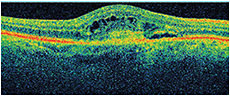

Visual acuity measured 20/100+1 OD and 20/25-2 OS. Fluorescein angiography revealed a subfoveal classic choroidal neovascular membrane with leakage OD. Figure 1 shows his OCT at baseline. He received three monthly bevacizumab injections OD with limited response in vision and on OCT, (Figures 2-3). He then received aflibercept OD. Despite missing a monthly appointment, the patient had noted improvement in vision at 2 months after injection, and the examination documented improvement in visual acuity and macular thickness on OCT (Figure 4).

Figure 3. OD, 1 month after bevacizumab injection number three, VA 20/100-1, CMT 378.

Figure 4. OD, 2 months after aflibercept injection, VA 20/60+2, CMT 285.